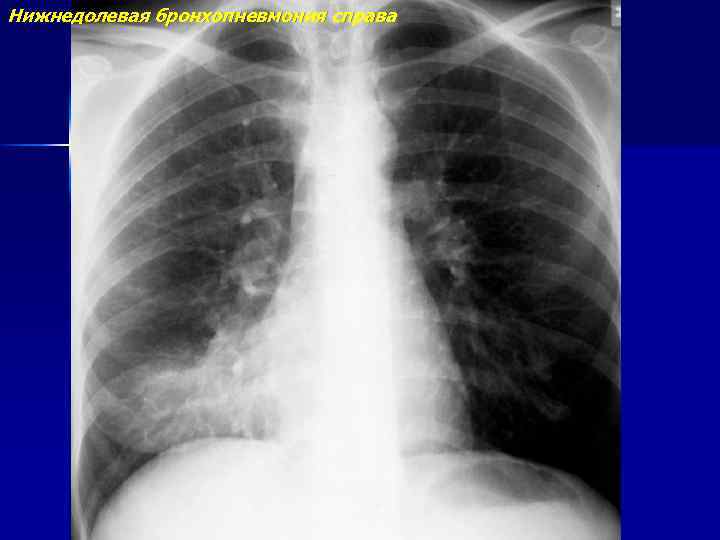

Бронхопневмония

Нижнедолевая бронхопневмония справа